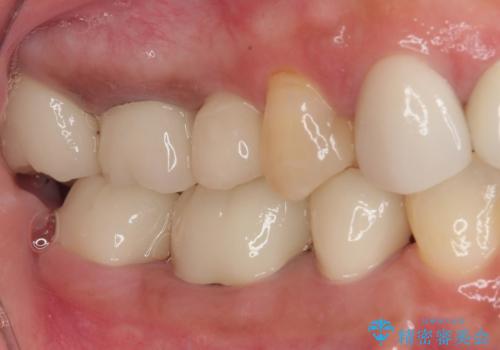

- 地元の歯科医院で治療を行っていたものの、難しいので都会に行くように指示をされたとのことで来院された患者様です。

右下のむし歯が歯肉縁下に及んでおり、歯周外科処置(歯冠長延長術)を行った上で、根管治療を行い、状態を整えて補綴治療を行うこととしました。

新幹線で通院をされていたため、極力診療回数を減らして、一度にまとめて多くの処置を行うことで負担を軽減しました。